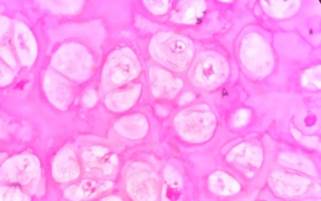

Histopathological examination revealed a bony lesion with

cartilaginous cap of increased thickness and cellularity. Cartilaginous

cap increased cellularity possess plump chondrocytes showing

binucleation forming nodules with mild nuclear enlargement, irregularity and

atypia. Cartilaginous cap undergoes endochondral ossification

as in a case of osteochondroma, suggesting the possibility of Secondary

peripheral atypical cartilaginous tumor from osteochondroma of tibia (Figure

4,5).

Figure

4. Histopathological

image showing cartilage undergoing endochondral osssification

(H&E stain, 10X).

5. Histopathological

image showing nodules of chondrocytes exhibiting mild atypia (H&E stain,

40X).